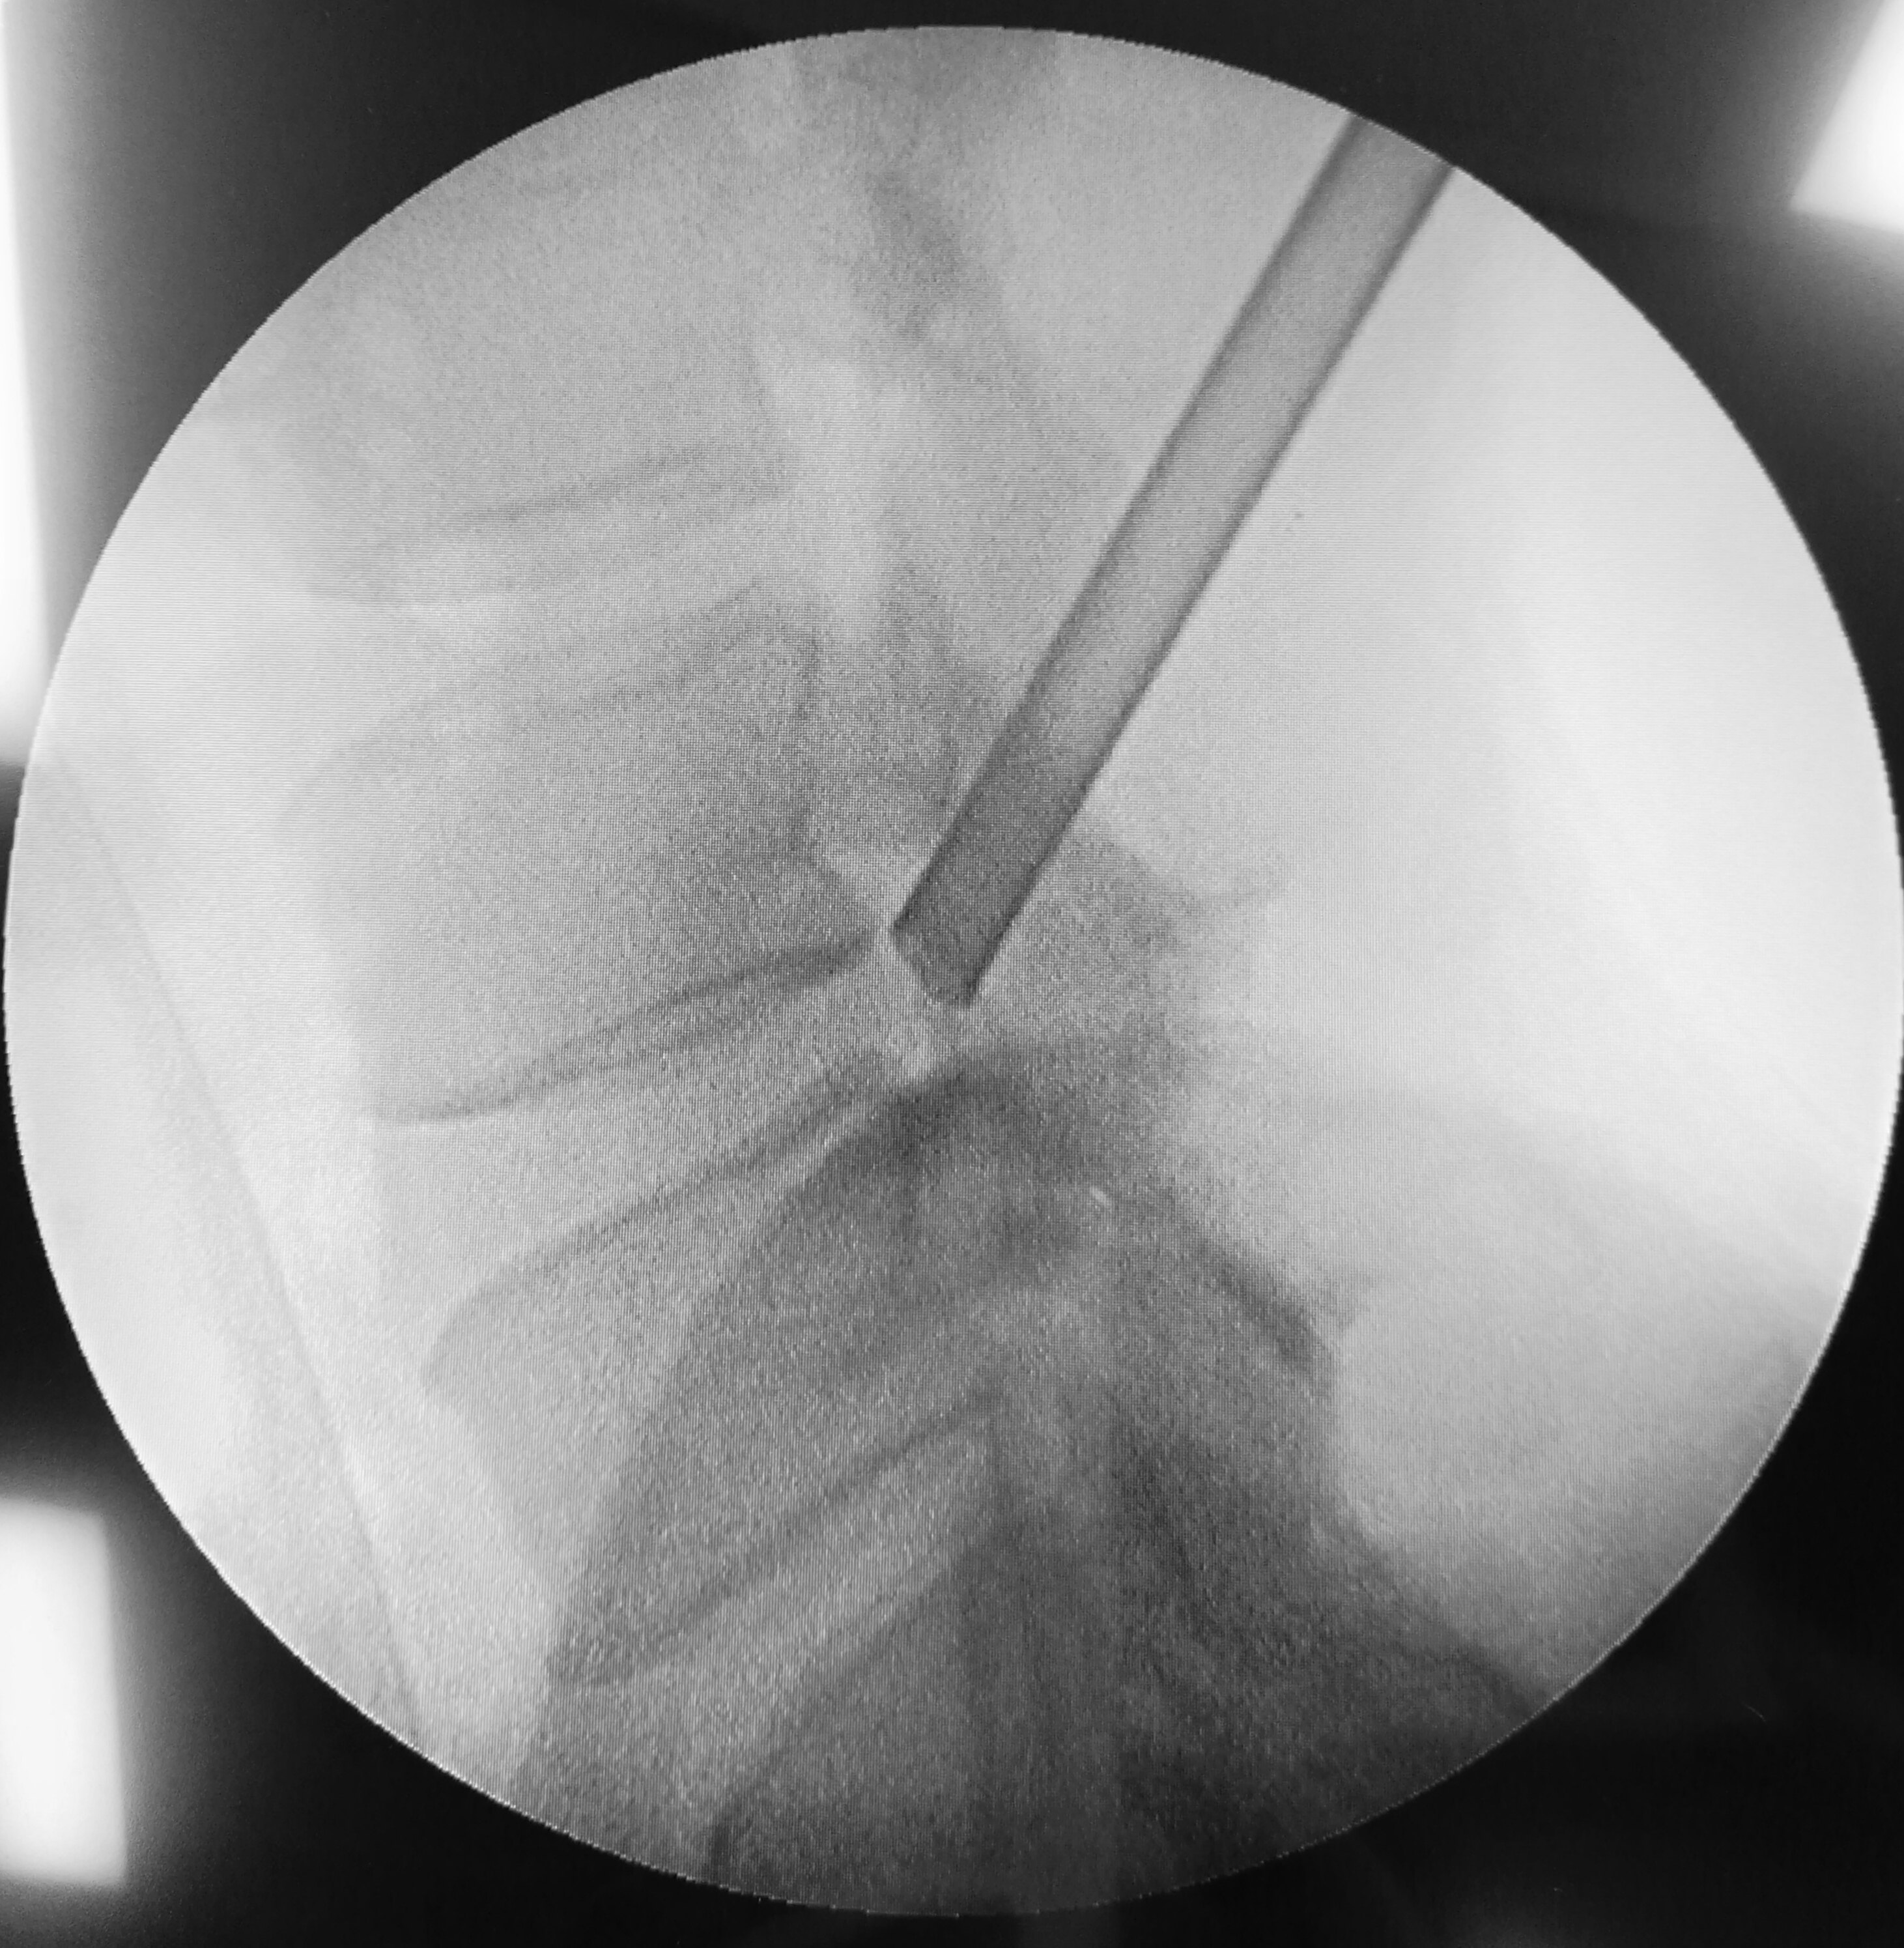

椎间孔镜(颈椎)

图片尺寸2667x2000